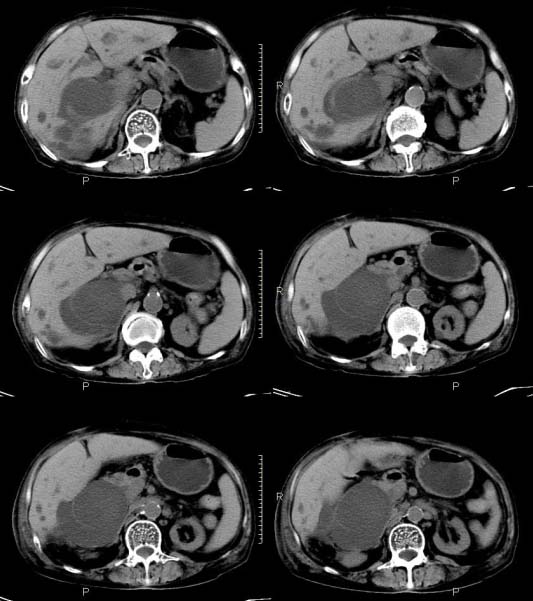

女,71岁,腹痛、腹胀、黄疸20余天,b超示肝内外胆管高度扩张内伴絮状物质(未提示梗阻部位或结石影),经抗炎解痉治疗后,肝功能有所好转,但胆道梗阻状态并未减轻。患者曾于1970年代做过胆囊切除术,1997年因胰腺炎而手术;且患者有糖尿病10余年。ct图片传了静脉期,未传动脉期了,最后一序列为3.2mm薄扫,请各位同仁仔细看看,确定一下胆管梗阻的部位,是炎性梗阻还是肿瘤性梗阻,是否与胰腺炎有关系,扩张胆总管中段前缘是否是胰管。请高手们最好用图示来指出梗阻部位。

扩张的胆管直达胰头,但胰头增大又不明显,且无异常密度影。考虑壶腹部占位。

支持2楼   非梗阻病变    胰管无明显扩张

肝内外胆管显著扩张,考虑先天性胆管囊肿(ⅳ型)。

肝内胆管远侧、近侧不比例扩张,以近侧为明显。胆总管扩张。考虑先天性胆管囊肿(ⅳ型)。